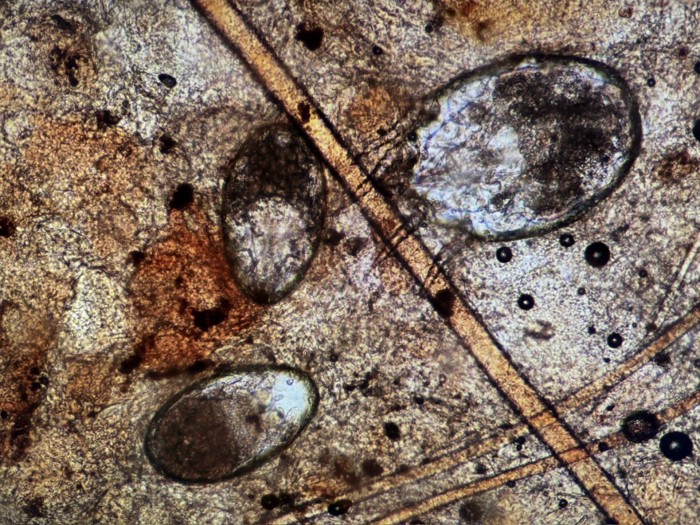

よって、動物病院に行き耳垢検査と呼ばれる、耳垢を顕微鏡で見る検査をします。

ミミヒゼンダニの虫体、もしくは虫卵が見つかった場合には耳ダニと診断されます。